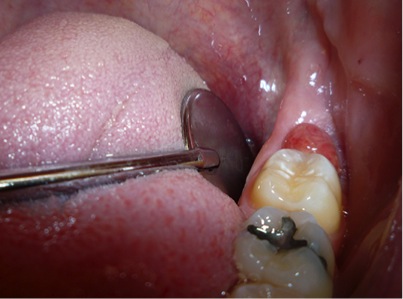

Fig 8. The angled handpiece of the CO<sub>2</sub> laser was held perpendicular to the target lesion.

Figure 8

2. The angled handpiece of the CO2 laser was held perpendicular to the target lesion (Figure 8) and the ablation of the inflamed tissue began (Figure 9). The dental surgeon was careful to avoid contact between the laser beam and the tooth enamel. (Note: In this case, the inflamed tissue was located distally from the involved molar. There was no direct contact of the beam with the tooth, as the surgeon was careful not to hit the enamel. However, if an operculum covers part of the tooth, an adaptive tool (for example, a wax spatula) needs to be inserted between the tissue and the tooth to prevent possible damage. For an inexperienced CO2 laser surgeon, it is important and highly recommended to always shield the tooth during the procedure.6)